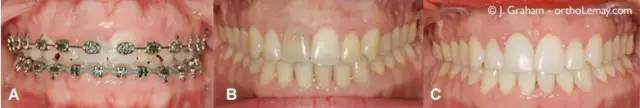

最终治疗效果

(A)侧面轮廓。(B)正面轮廓。(C)正畸完成后的微笑。微笑时不再露出牙龈,而且没有进行外科手术!

最终的咬合情况

(A)正在治疗的牙齿。(B)治疗结束后。(C)接受激光重塑后,牙龈看起来轮廓更好了。同时,全科牙医在右上中切牙(门牙)上做了贴面。

(A) 为治疗前严重的笑露牙龈情况。(B) 图是治疗结束时的样子。(C)是在中切牙(门牙)上贴了贴面后的情况。同时,还需注意到,为了改善下巴的形态,采用了外科手段(下颏成形术)。